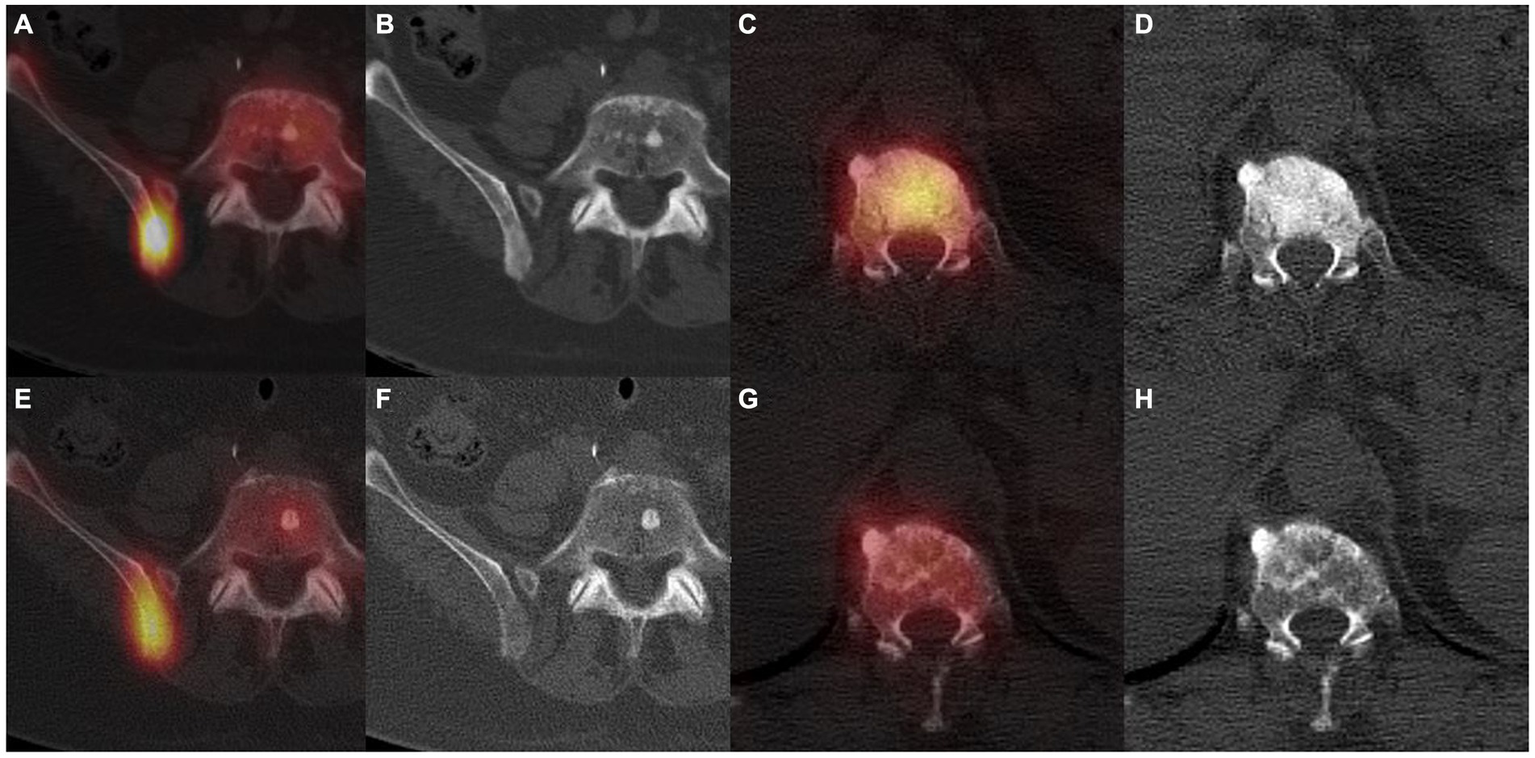

Figure 1

99mTc-HMDP SPECT/CT in a first patient with a bone metastatic prostate adenocarcinoma under first generation hormonotherapy for 2 years, showing a right posterior iliac sclerotic bone metastasis with a high uptake (A,B). Routine follow-up 6 months later showed shading of the iliac metastasis and less intense uptake (E,F), linked to a progression confirmed by a rising PSA and subsequent imaging. 99mTc-HMDP SPECT/CT in a second patient with a bone metastatic breast invasive lobular carcinoma, displaying a vertebral sclerotic metastasis with a high uptake at initial staging (C,D). Routine follow-up 12 months later showed a shadowing of the metastasis and a less intense uptake (G,H), indicative of a therapeutic response confirmed by clinical evolution and subsequent imaging.